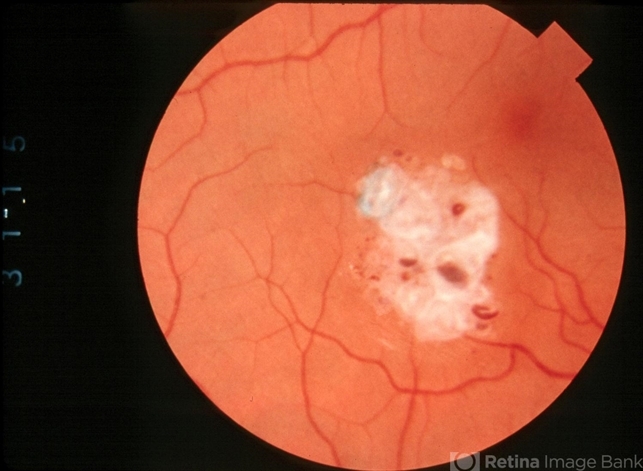

- cavernous hemangioma of the retina

- 32-year-old man with retinal cavernous hemangioma found on routine exam.